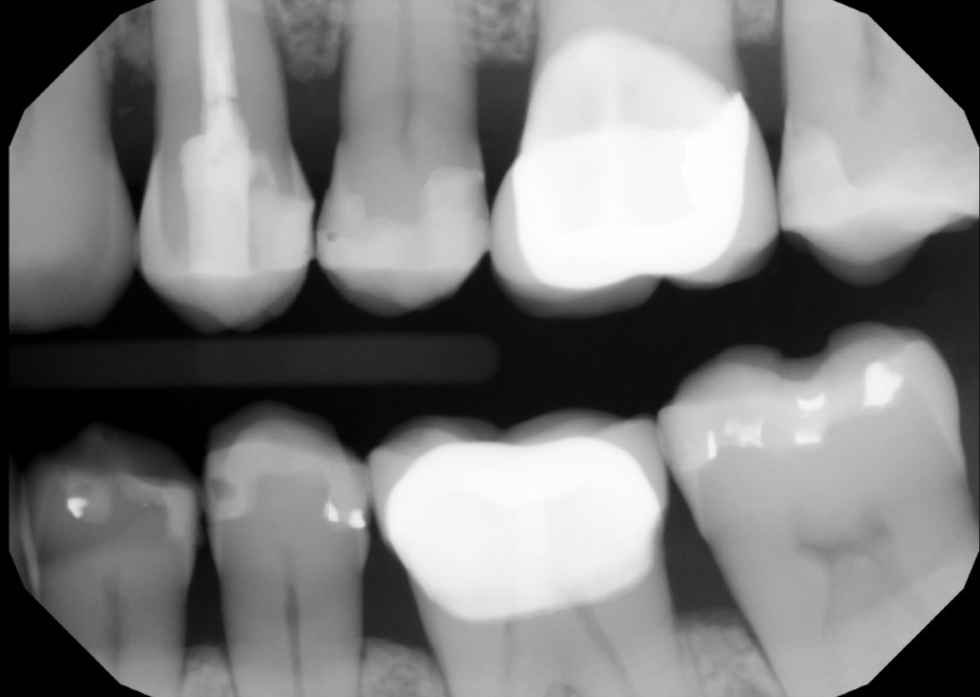

NS-RCT 2-Canal premolar

Pt presented with symptomatic irreversible pulpitis with normal apical tissue, due to secondary caries involvement. Unfortunately, there was a file separation at the apex due to the curvature. Since tooth was still vital, the prognosis of NS-RCT was still good according to literature. Pt was informed all the risks and prognosis. All NS-RCT and core B/U was done in one session.